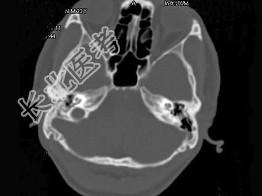

- 单项选择题男,23岁,右耳流脓十余年,右外耳道流脓,鼓膜穿孔,CT检查如图,最可能诊断为 ( )